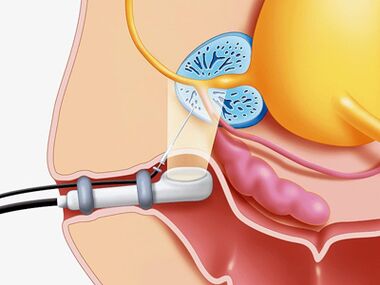

- Une biopsie au punch est réalisée en cas de suspicion d'abcès, d'hyperplasie bénigne et de cancer de la prostate.

- Pour clarifier les causes du développement de l'obstruction sous-vésiculaire, un examen radiologique et endoscopique est réalisé.

- En cas de processus inflammatoire long et fluide, il est recommandé de réaliser une urétrocystoscopie.